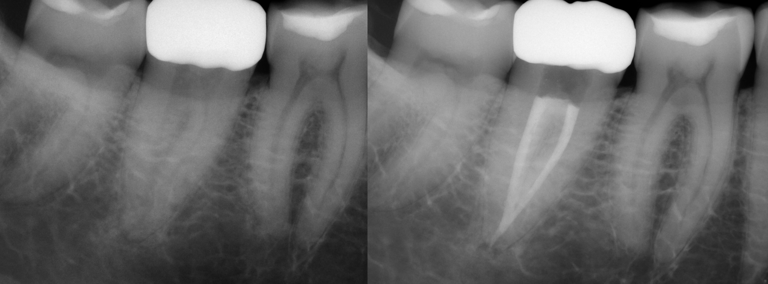

Gallery 1: Initial Cases

Initial Root Canal Cases with preoperative and postoperative radiographs.

#31 RCT

#31 RCT with C-Shaped Canals